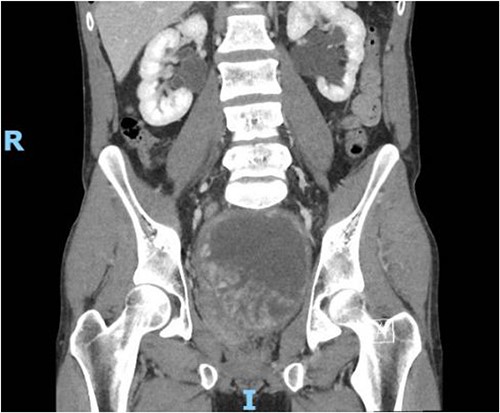

In contrast to the prior biopsies, the resection specimen revealed the tumor harbored areas with marked nuclear atypia, high cellularity, mitoses, and necrosis. A diagnosis of poorly differentiated leiomyosarcoma was rendered, with margins free of tumor (closest was 2 mm) (Fig. 3). The patient had an uneventful recovery. He reported complete resolution of his obstructive symptoms 1 month after the procedure. Given his recent diagnosis of high-grade cancer, adjuvant conventional fractionation radiotherapy targeting the postoperative bed without any elective nodal coverage was undertaken. Two months after radiotherapy, he reported having a normal urinary stream, good erections with penetration and forward ejaculation. He has now been on follow-up for the past 24 months with six monthly CT scans with no evidence of recurrence (Fig 4).

Contrast CT pelvis at 20 months post-surgery showing no residual disease.